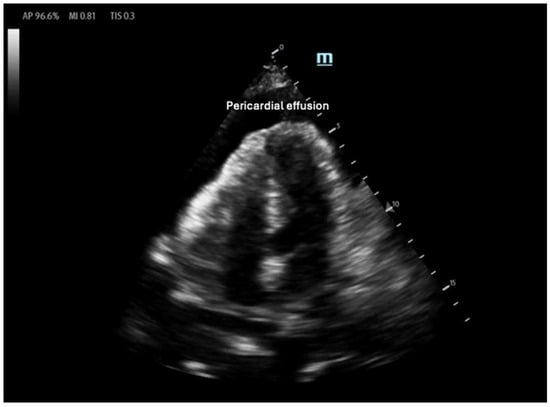

3.2. Right Ventricular Contractility

Right ventricular (RV) contractility is essential for maintaining right-sided cardiac output, ensuring blood supply to the pulmonary vasculature and subsequently to the left heart. Unlike the LV, the RV contracts primarily through longitudinal muscle fiber shortening, inward free wall movement, and LV-dependent contraction [32]. As a result, RV contraction occurs predominantly in a longitudinal rather than radial manner. Due to the RV’s greater compliance compared with the LV, its contractility and CO are highly influenced by changes in afterload, which will be discussed in the next section. External pressure changes, such as those seen in cardiac tamponade, can also significantly impact RV function. In tamponade, pericardial fluid compresses the heart chamber, elevating RV diastolic filling pressure and reducing RV output [33]. Owing to the RV’s increased compliance, the RA and the RV are the first chambers to collapse under increased pericardial pressure. Therefore, RA/RV collapse on bedside POCUS in the presence of a pericardial effusion should raise the suspicion of tamponade (Figure 5) [34].

Anechoic pericardial effusion in apical 4-chamber view.